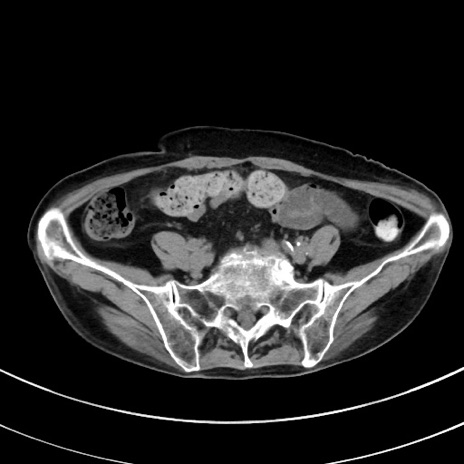

症例33(横断像)

【症例】70歳代 女性

【主訴】心窩部痛

【現病歴】延髄病変の精査・加療にて神経内科入院中。本日より心窩部痛あり。

【身体所見】右下腹部を中心に圧痛と反跳痛あり。

【データ】WBC 10900、CRP 0.02